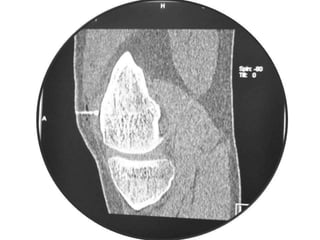

Osteoid Osteoma

• CT may detect the nidus, whereas

roentgenograms show only sclerosis.

Osteoid Osteoma - CT

• CT is more accurate than MRI.

• CT helped in confirming the diagnosis of

osteoid osteoma in 74% of cases.

• Szendroi et al reported accuracies of about

66% in the diagnosis of intra-articular lesions

and 90% in extra-articular lesions.

• To date, CT scanning is the primary

investigational tool for the definitive diagnosis

of osteoid osteoma.

Osteoid Osteoma • CTmay detect the nidus, whereas roentgenograms show only sclerosis.

Osteoid Osteoma -CT • CT is more accurate than MRI. • CT helped in confirming the diagnosis of osteoid osteoma in 74% of cases. • Szendroi et al reported accuracies of about 66% in the diagnosis of intra-articular lesions and 90% in extra-articular lesions. • To date, CT scanning is the primary investigational tool for the definitive diagnosis of osteoid osteoma.